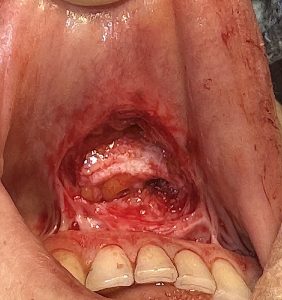

Pocket preparation (critical step)

- Intraoral vestibular approach

- Create a precise, snug pocket

- Superficial plane or deep plane

- Deep subcutaneous superficial to mentalis muscle with fold release

- Have to undermine the fold

- Under the mentalis muscle above the periosteum (deep plane)

- Insert graft horizontally across the fold